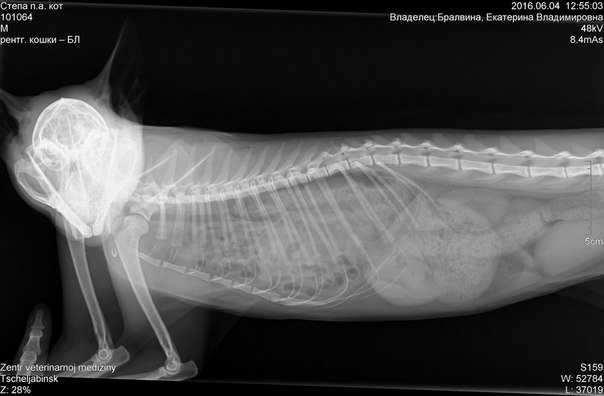

Добрый день, уважаемые формучане. Кратко история такова: взяла на передержку кота. Сказали, здоров. Обратила внимание, что он дышит странно, особенно после еды и мало двигается (играет, но быстро устаёт). Решила, что это его особенность (кошек не держала давно). На всякий показала его врачу, сделали снимок… Врач был крайне удивлён – на снимке тонкий кишечник в грудине, а лёгких практически не видно. Подозрение на разрыв диафрагмы, но тогда вопрос – как он вообще живёт? Показала его второму врачу, он сказал, надо сделать ещё снимок с контрастным веществом.

Учитывая состояние кота, я не уверена, что насильное кормление раствором не ухудшит резко его состояние. Сейчас кот как-то приспособился жить – стул регулярный, аппетит отличный, шерсть блестит, сказать, что он мучается не скажу – играет и мурлыкает. При этом всё же видно, что ему тяжеловато, особенно после еды. Вопроса у меня два:

1. Есть ли смысл в насильственной процедуре рентгена с контрастом, т.к. и без этого видны проблемы, которые можно решить только операбельно. Что может дать этот анализ?

2. Каковы шансы удачного исхода операции? Не окажется ли, что после неё у кота возникнут более серьёзные проблемы, чем есть сейчас.